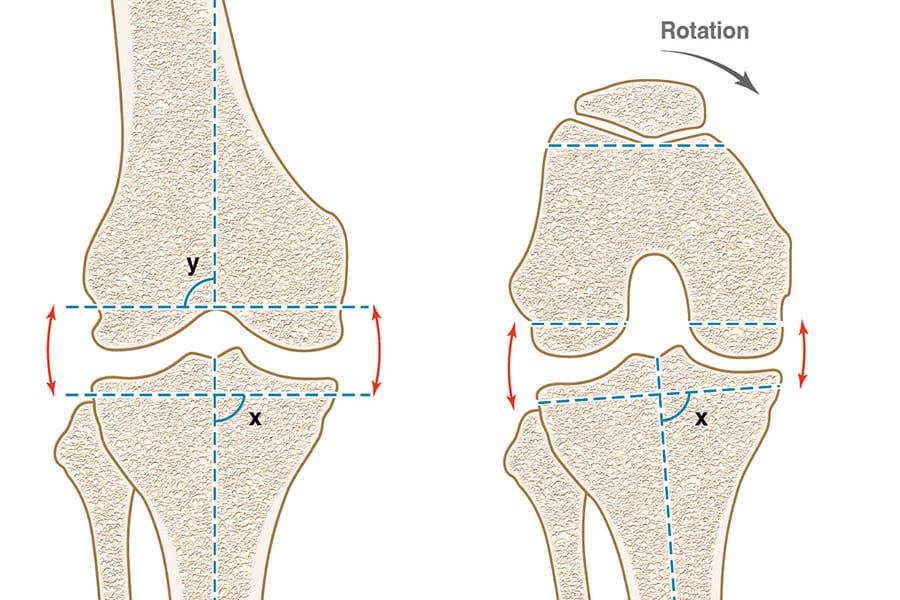

The clinical articles address complementary dimensions of arthroplasty science. Implant safety and fixation are explored through studies on the evolution of metal ions following knee prosthesis implantation and line-to-line cementation in hip arthroplasty, with attention to the "French Paradox". Reconstructive complexity is examined in severe post-traumatic and post-arthroplasty acetabular defects, extending beyond existing classifications. Patellofemoral surgery is contextualized through The Lyon contribution to patellofemoral surgery, tracing the legacy from Albert Trillat to Henri Dejour. The issue is further complemented by a dedicated analysis of ligament balancing and alignment.